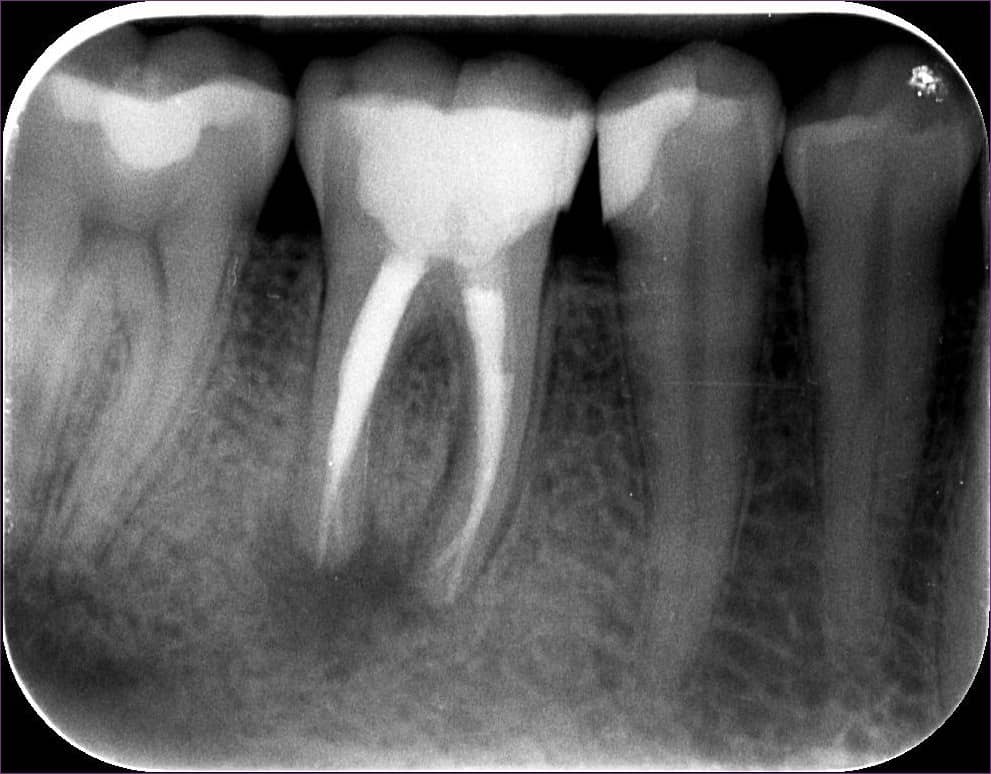

A másik különbség, hogy az egyik erős fájdalommal jár, a másik legtöbbször csak némi érzékenységgel. Így az első típusú gyulladást gyorsan orvosolhatjuk, a másik esetén azonban a gyulladás alattomosan végezheti pusztító munkáját, és sokszor csak a fogászati kontrollokon derül fény jelenlétükre – egy röntgenfelvételnek köszönhetően.

A gyökércsúcs körüli gyulladás jól megfigyelhető a fenti röntgenfelvételen: a sötét folt a jelzi, hogy a szövetek gyulladásban vannak.